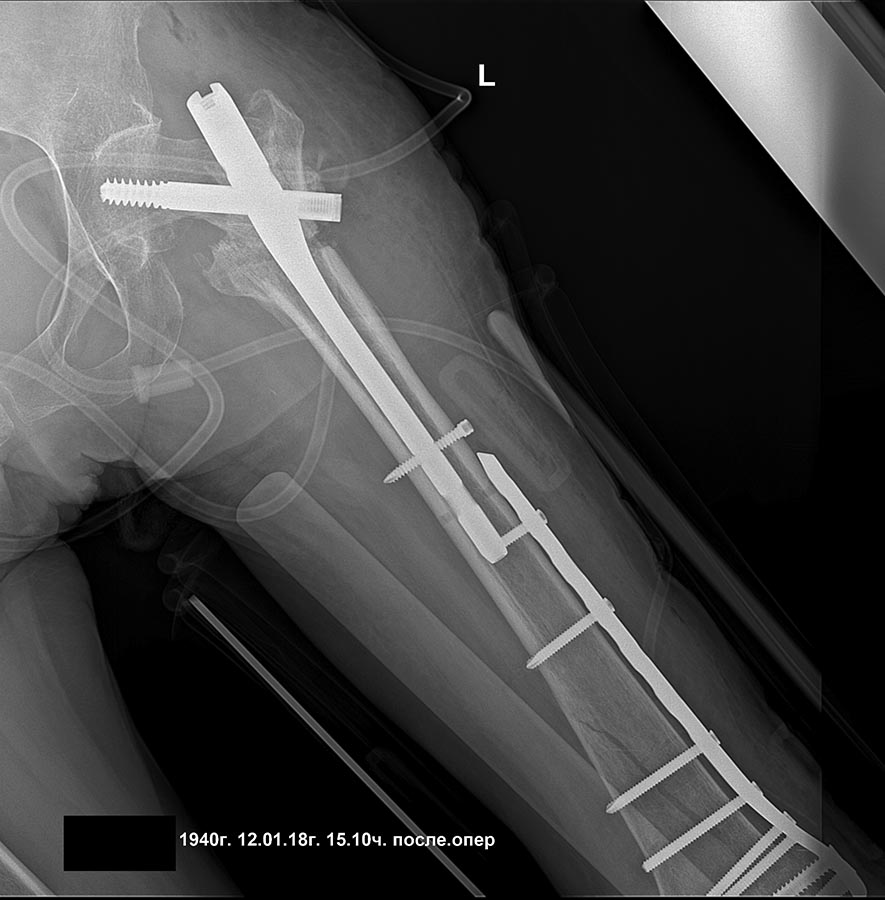

[Ortho] Сросшийся чрезвертельный и перелом н\3 бедра

добрый день! вроде все получилось сделать,закрыто,чрезкожная остеотомия.

дистальная пластина тоже малоинвазивно